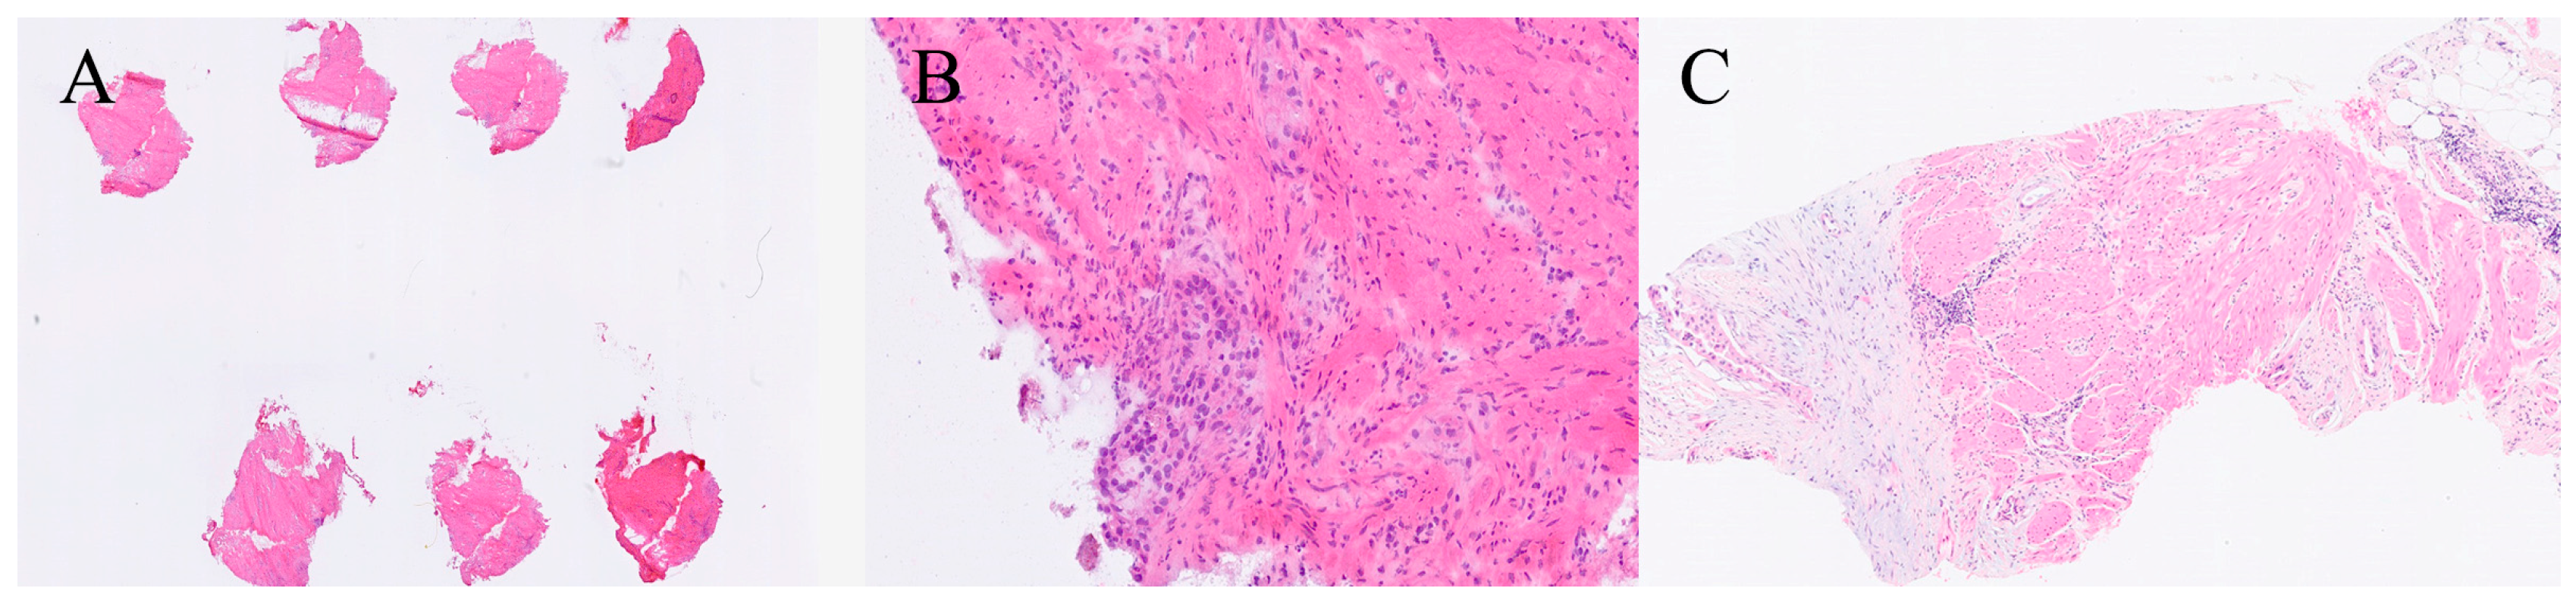

Analytical errors are the most frequent and may stem from non-representative or suboptimal sampling, difficulty cutting calcified or fibrotic tissue (Figure 3), or loss of tissue during freezing. Artefactual distortion—most often from freezing, tissue compression, or incomplete embedding—can obscure cytologic and architectural detail, predisposing to misinterpretation. Interpretative errors include misclassification of benign versus malignant lesions, incorrect tumour typing, or inaccurate margin assessment. The time-sensitive environment of intraoperative consultation and inherently limited tissue quantity amplify these risks, underscoring the need for cautious correlation with permanent sections.

5.3. Post-Analytical Errors

Post-analytical errors generally involve communication failures, such as delayed or unclear reporting of FS findings to the surgical team, which can compromise intraoperative decision-making [3]. Structured reporting templates and closed-loop communication systems have been shown to reduce such discrepancies, particularly in high-volume centres.

The cumulative impact of these errors can be substantial. An inaccurate FS diagnosis may lead to inappropriate operative steps, such as unnecessary extension of resection, incomplete tumour clearance, or premature termination of surgery [43]. These misjudgements can result in increased morbidity, a need for reoperation, or suboptimal oncological outcomes. Continuous quality assurance, standardised documentation, and explicit acknowledgment of technical limitations (see Pitfalls and Limitations) remain essential to minimise diagnostic error and maintain patient safety [3,35,44].